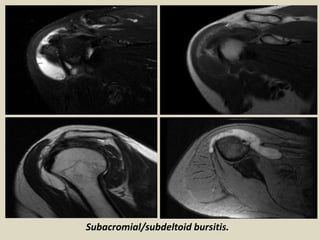

Subacromial/subdeltoid bursitis.